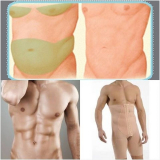

Lipoaspiração a Laser

Você merece a qualidade e comprometimento entregues pela equipe deste consultório médico e se neste momento está à procura de uma equipe que realize lipoaspiração a laser saiba que a FF Cirurgia Plástica disponibiliza de imediato este serviço para você!

Lipoaspiração a laser: atendimento eficiente e com qualidade que você sempre buscou!

Neste consultório médico você encontrará profissionais eficientes e com experiência de excelência. Usufrua de bom atendimento, através dos melhores preços do mercado e de assistência especializada sempre à sua disposição! Leve as suas dúvidas, converse com a equipe da FF Cirurgia Plástica. Contrate bons serviços e sinta-se mais seguro para cuidar da saúde.